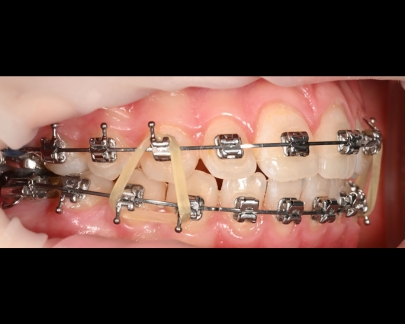

Sunt benzi elastice mici, din latex, folosite pentru corectarea mușcăturii și intercuspidarea dinților.

Elasticele se atașează de brackeții dinților superiori, respectiv inferiori și vin în diferite dimensiuni și grade de forță.

![]() | ![]() |

Elasticele ortodontice corectează raportul dintre maxilar și mandibulă (mușcătura). Sunt purtate conform indicațiilor medicului și sunt esențiale în multe tratamente pentru alinierea corectă a arcadelor.